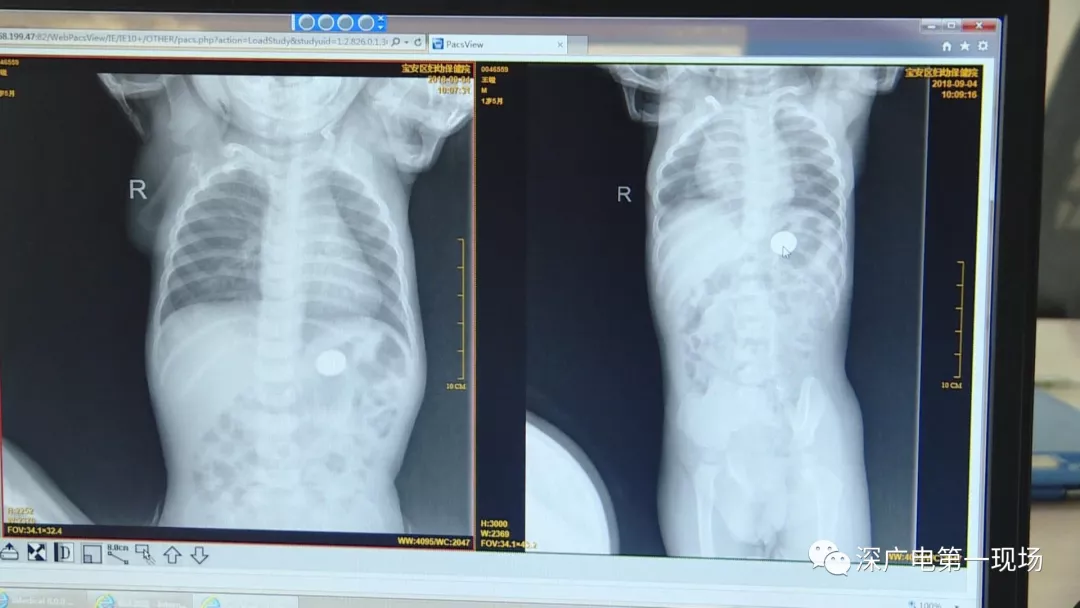

9月4号,一名1岁零5个月的男婴因在家中摔伤,被父母送到了宝安区妇幼保健院,医生诊断为左侧尺桡骨骨折。在进行全麻手术之前,院方例行对婴儿进行了周身检查。手术前,儿外科医生赵冠聪在查看患者的胸片时,发现这名婴儿的胃部有一枚硬币大小的暗影。

胃部取出一角硬币

已吞咽半月之久

经过两个小时的时间,儿科医生郭景涛为患儿取出了藏在胃底的一角钱硬币。目前,患儿已经痊愈出院。